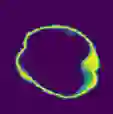

Despite the state-of-the-art performance for medical image segmentation, deep convolutional neural networks (CNNs) have rarely provided uncertainty estimations regarding their segmentation outputs, e.g., model (epistemic) and image-based (aleatoric) uncertainties. In this work, we analyze these different types of uncertainties for CNN-based 2D and 3D medical image segmentation tasks. We additionally propose a test-time augmentation-based aleatoric uncertainty to analyze the effect of different transformations of the input image on the segmentation output. Test-time augmentation has been previously used to improve segmentation accuracy, yet not been formulated in a consistent mathematical framework. Hence, we also propose a theoretical formulation of test-time augmentation, where a distribution of the prediction is estimated by Monte Carlo simulation with prior distributions of parameters in an image acquisition model that involves image transformations and noise. We compare and combine our proposed aleatoric uncertainty with model uncertainty. Experiments with segmentation of fetal brains and brain tumors from 2D and 3D Magnetic Resonance Images (MRI) showed that 1) the test-time augmentation-based aleatoric uncertainty provides a better uncertainty estimation than calculating the test-time dropout-based model uncertainty alone and helps to reduce overconfident incorrect predictions, and 2) our test-time augmentation outperforms a single-prediction baseline and dropout-based multiple predictions.